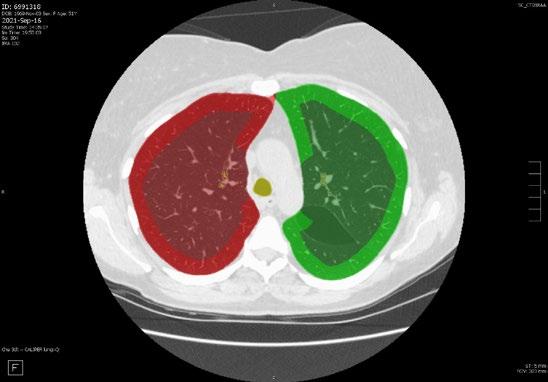

Radiogenomics Relationship of Nonsmall Cell Lung Cancer: Preliminary Results

Keywords: Cancer, lung, radiogenomics, radiology.

BACKGROUND AND AIMS

Radiomics, an emerging paradigm in medical imaging, entails the quantitative analysis of tumour features, and has exhibited potential in predicting treatment responses and outcomes. Furthermore, within the domain of -omics assessments, the significance of comprehensive genetic evaluation in non-small cell lung cancer (NSCLC) is on the rise, influenced by both biological and therapeutic considerations.

The aim of this study was to correlate radiomics features with the genetic results obtained from liquid biopsy in patients with lung tumours. The prediction of tumour genetics in radiomics relies on the presumption of conducting a non-invasive evaluation of molecular characteristics in tumour tissues, which can be challenging in certain tumour types, such as NSCLC. Therefore, in this context, the authors considered it pertinent to explore and generate hypotheses regarding the technical feasibility of identifying associations between genomics acquired through liquid biopsy assessments and radiomics.

MATERIALS AND METHODS

This observational, prospective study integrated radiomic perspectives using CT and genomic perspectives, through next-generation sequencing applied to liquid biopsies.

The authors included 62 patients with NSCLC who underwent pre-surgery CT (Revolution™ 128 MDCT, GE HealthCare, Chicago, Illinois, USA) at the Radiology Department of Campania University Luigi Vanvitelli, Naples, Italy. Every patient for whom liquid biopsy was performed gave informed consent for the genetic analysis. For the radiomic analysis, image processing CT volumes were manually delineated using ITK-SNAP 3.8.0 (University of Pennsylvania, Philadelphia, USA). Radiomics features (first order: Gray Level Co-occurrence Matrix, Gray Level Run Length Matrix, Gray Level Size Zone, Gray Level Dependence Matrix, and Neighbouring Gray Tone Difference Matrix) were computed using Pyradiomics1 in Python 3.7 (Python Software Foundation, USA) environment.

Radiomic features were derived from CT images, and genetic assessments were performed using a comprehensive panel targeting 523 cancerrelated genes. For the statistical analysis, association between radiomic features and gene mutations were assessed using feature importance based on receiver operating characteristic curve analysis; moreover, a machine learning approach based on support vector machine was used to evaluate the ability of radiomic features to predict gene mutations.

Associations between radiomic features and genetic mutations were established using the area under the receiver operating characteristic curve. Machine learning techniques, including support vector machine classification, aimed to predict genetic mutations based on radiomic features. The prognostic impact of selected gene variants was assessed using Kaplan–Meier curves and log-rank tests.

RESULTS

Sixty-two patients underwent screening, with 53 being comprehensively characterised radiomically and genomically. This group was predominantly male (68.4%), and adenocarcinoma was the prevalent histological type (73.7%). Most patients exhibited ECOG Performance Status of 0 or 1 (87.7%), and 91.2% had a history of former or current smoking. Disease staging was distributed across I–II (38.6%), III (31.6%), and IV (29.8%). Significant correlations were identified with mutations

Abstract ● ECR 2024 24 Radiology ● April 2024 ● Creative Commons Attribution-Non Commercial 4.0

of ROS1 p.Thr145Pro (shape_Sphericity), ROS1 p.Arg167Gln (glszm_ZoneEntropy, firstorder_TotalEnergy), ROS1 p.Asp2213Asn (glszm_GrayLevelVariance, firstorder_ RootMeanSquared), and ALK p.Asp1529Glu (glcm_Imc1). Patients with the ROS1 p.Thr145Pro variant demonstrated markedly shorter median survival compared to the wild-type group (9.7 months versus not reached; p=0.0143; hazard ratio: 5.35; 95% confidence interval: 1.39–20.48).

CONCLUSION

This study contributes to advancing the prediction of cancer genetics through the application of non-invasive radiomic techniques. The prediction of tumour genetics in radiomics hinges on the assumption of conducting a non-invasive assessment of molecular characteristics in tumour tissues, which can pose challenges in certain tumour types, such as NSCLC. Therefore, within this context, the authors deemed it relevant to explore and formulate hypotheses regarding the technical feasibility of identifying associations between genomics obtained through liquid biopsy assessments and radiomics.

Specific radiomic features illustrate the capability to predict non-synonymous mutations of ROS1 and ALK in patients with NSCLC. Investigating the prediction of cancer genetics using non-invasive radiomic techniques represents an innovative frontier in scientific research, which is currently undergoing extensive investigation. Research on the use of conventional CT features and CT image-based radiomic features to predict the gene mutation status of lung cancer is still in its nascent stages.

The integration of radiomic techniques in predicting cancer genetics holds potential, but is constrained by cost and technological limitations. Despite these challenges, the authors’ study explores the relationships between genomics and radiomics, revealing specific genetic variants associated with radiomic features. While acknowledging limitations, particularly the small sample size and the lack of actionable mutations, this research lays the groundwork for broader investigations aiming to link radiomics and genomics in NSCLC. The ultimate objective is to improve prognostic accuracy and refine therapeutic strategies. ●